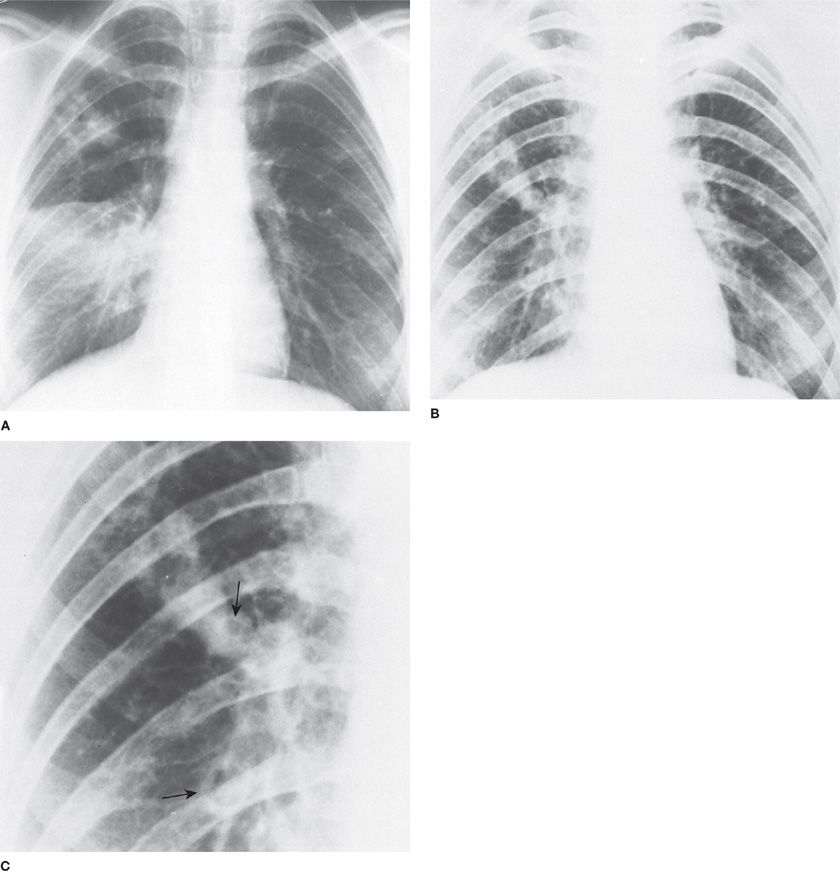

Aspergillus, Candida, and Other Opportunistic Mold Infections of the Can Mold Cause Lung Infections Most strains of this mold are harmless, but a few can cause serious illnesses when people with weakened immune systems,. It's almost impossible to completely avoid aspergillus mould. Invasive mold infections can cause significant morbidity and mortality in immunocompromised and critically ill patients;. Chronic pulmonary aspergillosis (cpa) is a fungal infection of the lungs that’s caused by aspergillus, a common. Can Mold Cause Lung Infections.